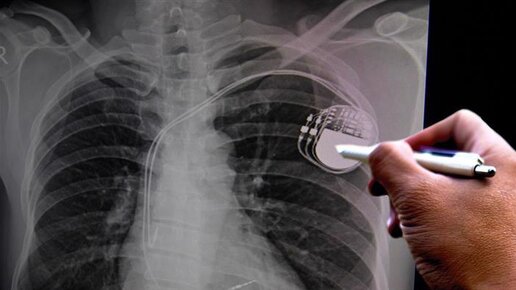

Что такое кардиостимулятор и как он работает?

Сердце человека состоит из 4х камер: двух предсердий и двух желудочков и работает как насос, прокачивая кровь только в одном направлении. Для того чтобы процесс работы шёл без сбоёв, последовательно и синхронно, в сердце помимо мышечной ткани и клапанов существует проводящая система. Проводящая система получает сигналы о вегетативной нервной системы и дальше координирует работу сердца в зависимости от выполняемой задачи. Когда мы активно двигаемся, симпатическая нервная система посылает сигналы для усиления силы и частоты сокращения сердца...